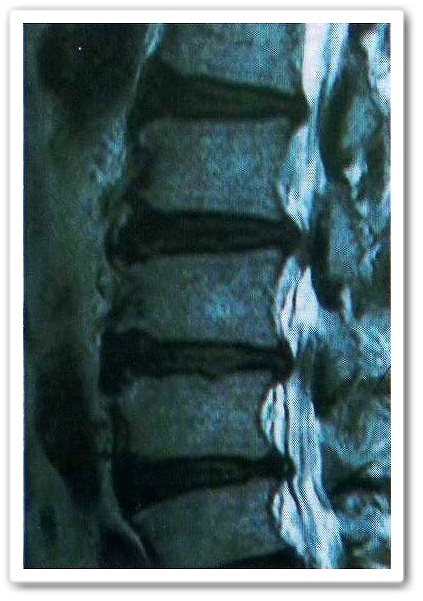

特に上からの骨2番目と3番目の骨に注目してみてください。

一番白く写っているのが神経ですがこの方の神経は途中で途切れているのが分かります。

この状態が脊柱管が狭窄(狭く)されているよう

すがはっきりと見て分かります。